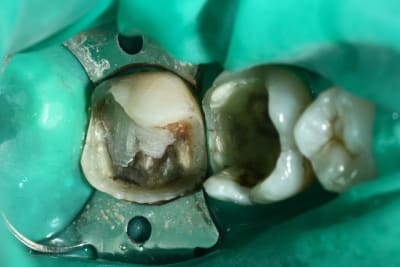

la radio et la photo a 1 mois

Faut avouer qu'ici l'indication du composite sur la 6 est quand même un peu "couillu", en distal par contre il reste une radio clarté: carie résiduelle ou épaisseur de colle importante, en tous cas ça peut fragiliser la suprastucture.